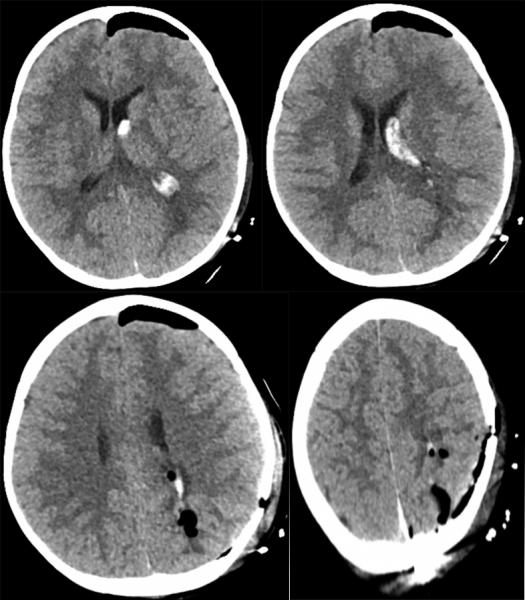

患儿黄某因发热、伴意识障碍入院求诊,经儿科初步诊治,完善颅脑CT后提示:颅内出血。接到值班医师电话后,作为“西部之光”访问学者研修归来的神经外二科副主任田志一边赶往病房一边对患儿的情况进行详细询问,凭借多年的手术经验,判断极有可能是一例颅内血管畸形导致的颅内出血,如不及时清除血肿和处理畸形血管团,患儿随时可能出现脑疝,导致死亡。

术前检查提示脑血管畸形